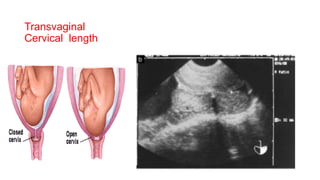

Transvaginal Cervical length

•Normal 3-4cm and no funnelling

•Measuring cervical length using transvaginal

ultrasonography is a useful tool to predict the risk of

preterm birth in low- and high-risk pregnancies.

• At 18-22 weeks

• CL <25 mm

Transvaginal

Cervical length

How short is too short

Cervical Length RR of PTD

<35mm 2.35

<30mm 3.79

<26mm 6.19

<22mm 9.49

<13mm 13.99